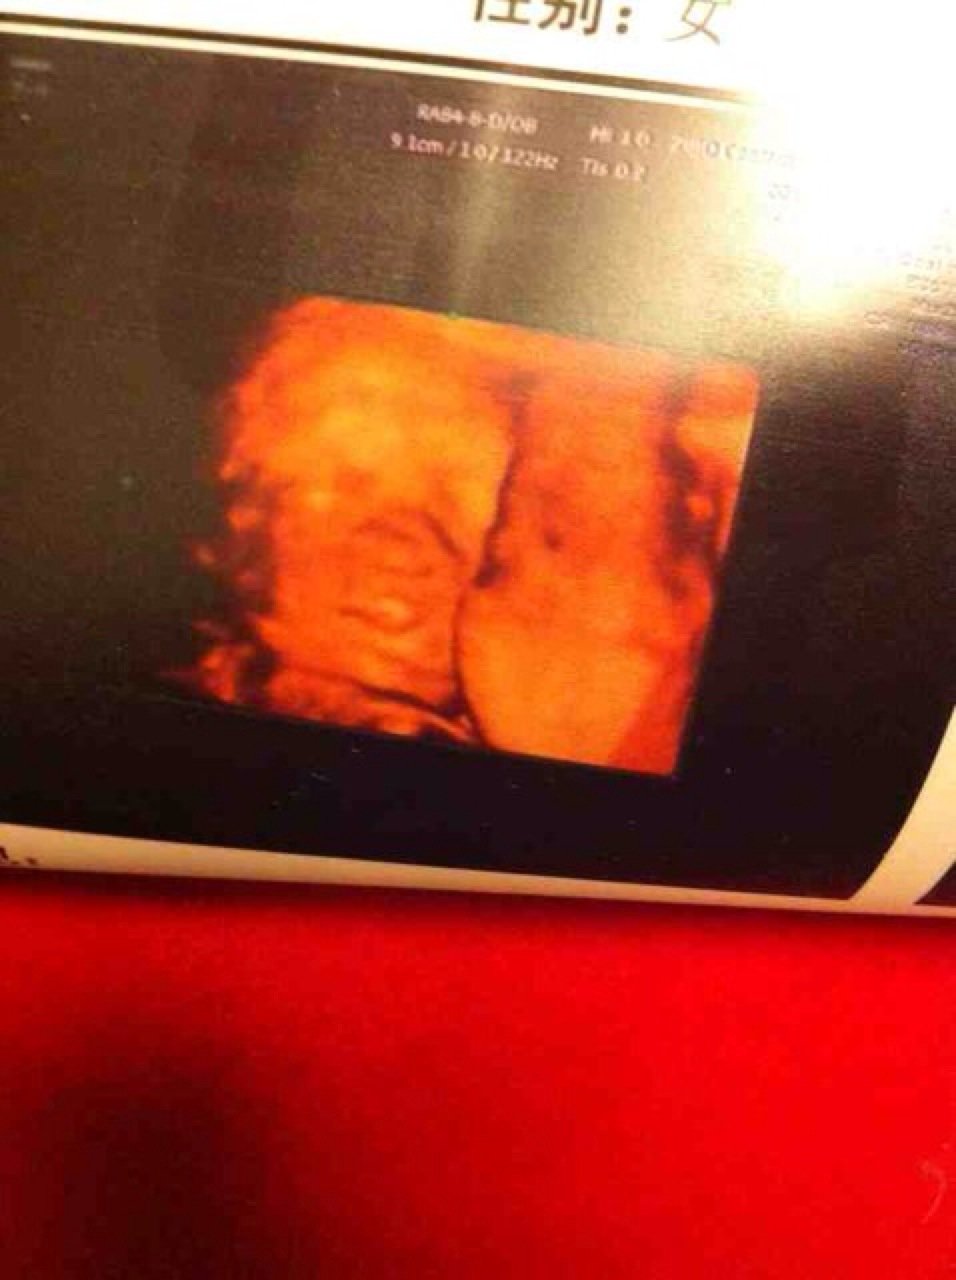

请大夫帮忙看下24周做的胎儿四维彩超图,感觉胎儿鼻子发育欠佳,但检查时大夫并没有说有什么异常 点击展开 匿名用户 2014-04-23 16:01 为您推荐: 其他回答 病情分析: 你好,这个问题考虑是难以观察的, 指导意见: 目前描述的情况我建议顺其自然,是先天性的症状。 白其雨_6xwx 2014-04-24 15:23 相关问题 怀孕32周,今天去检查大夫说尿蛋白高,不知道对胎儿有影响吗? 我怀孕六周孕酮是25 73ng/mL,大夫说我孕酮低,我想知道我这样会对胎儿接下来的发育有什么影 彩超检查显示胎儿双顶径8 5,股骨长7 6,大夫说也就35周,可是应该有36周了,是不是孩子太小了